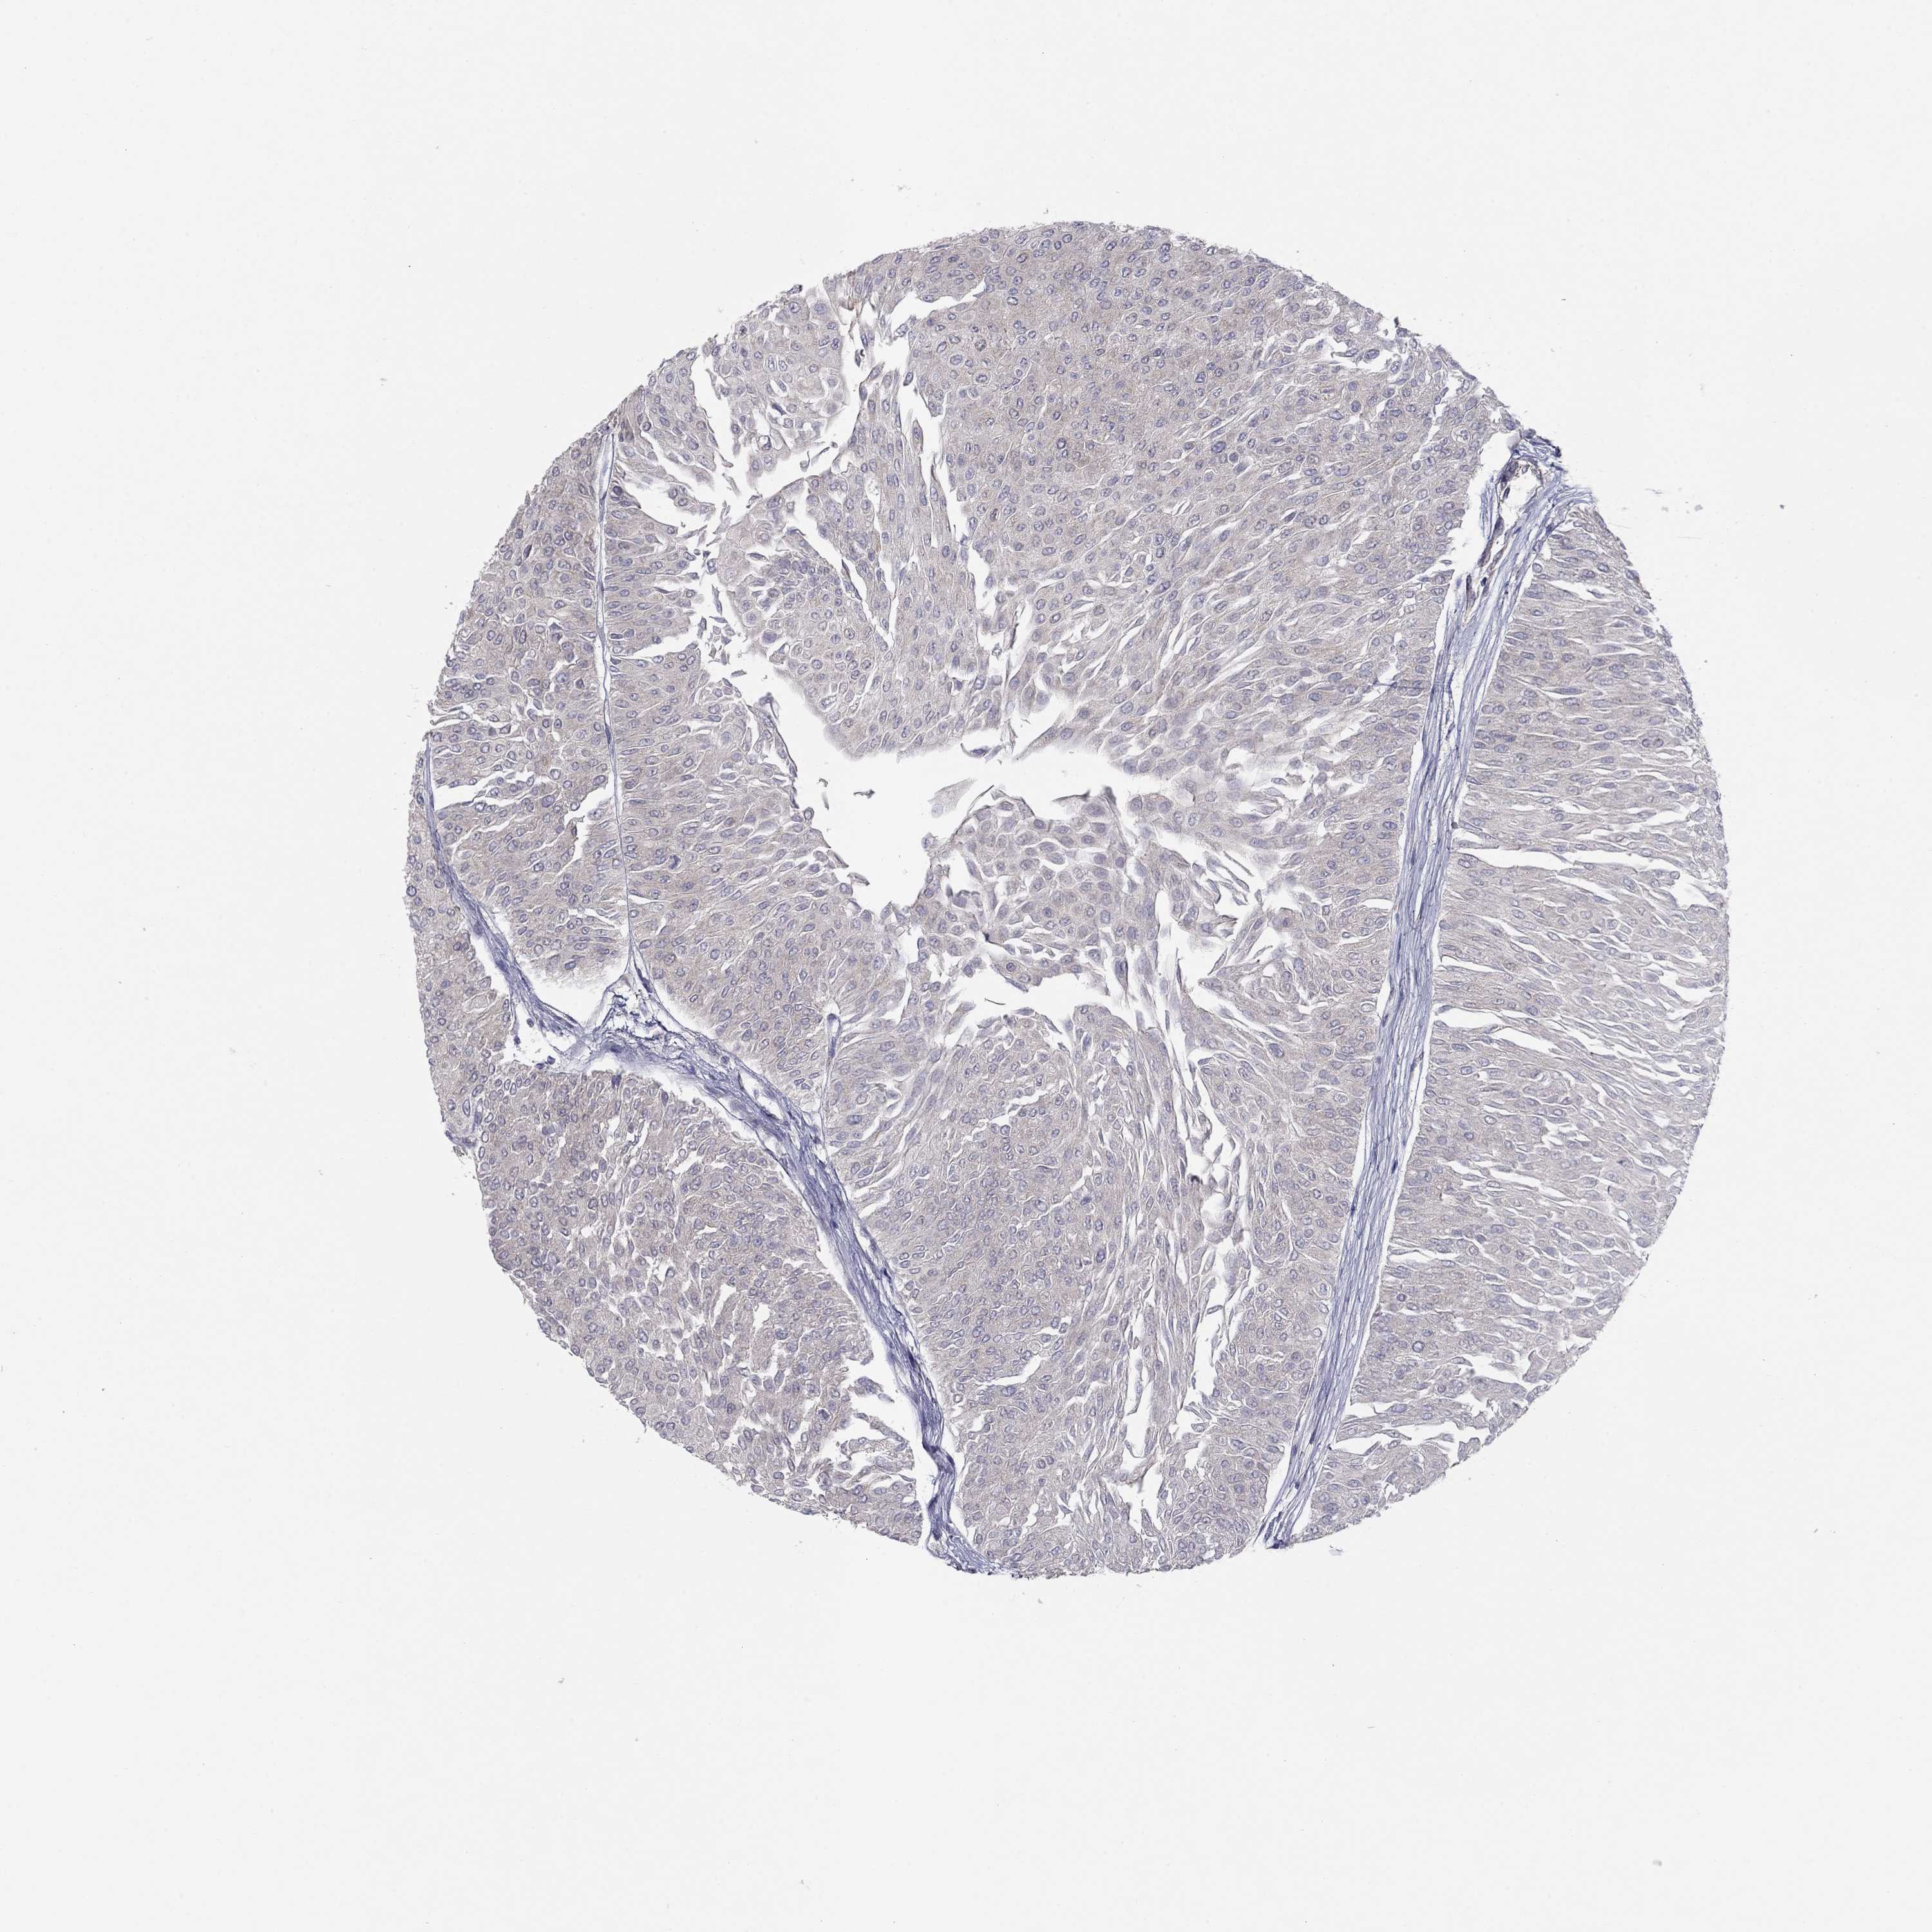

UROTHELIAL CANCER - Protein expressioni

A mouse-over function shows sample information and annotation data. Click on an image to view it in a full screen mode. Samples can be filtered based on level of antibody staining by selecting one or several of the following categories: high, medium, low and not detected. The assay and annotation is described here.

Note that samples used for immunohistochemistry by the Human Protein Atlas do not correspond to samples in the TCGA dataset.

Antibody stainingi

Antibody staining in the annotated cell types in the current human tissue is reported as not detected, low, medium, or high, based on conventional immunohistochemistry profiling in selected tissues. This score is based on the combination of the staining intensity and fraction of stained cells.

Each image is clickable and will lead to virtual microscopy that enables deeper exploration of all samples and also displays staining intensity scores, fraction scores and subcellular localization as well as patient and tissue information for each sample.

Antibody HPA076194

Staining

High

Medium

Low

Not detected

Intensity

Strong

Moderate

Weak

Negative

Quantity

>75%

75%-25%

<25%

None

Location

Nuclear

Cytoplasmic/membranous

Cytoplasmic/membranous,nuclear

Urothelial carcinoma, High grade

Urothelial carcinoma, Low grade